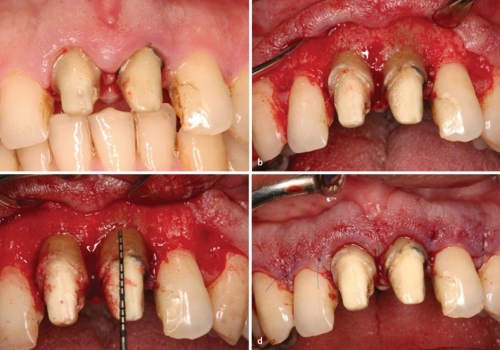

Diş tacının cərrahi uzadılması müxtəlif kliniki hallarda müxtəlif məqsədlərlə tətbiq edilən cərrahi müalicə prosedurudur. Bu metod estetik stomatologiyada “Gummy smile” (diş əti gülüşü) olaraq adlandırılan durumun ortadan qaldırılması məqsədilə geniş tətbiq olunur. Bu zaman kliniki hala bağlı olaraq bəzən yalnız diş əti, bəzən isə həm diş əti həm də sümükdən müəyyən miqdarda rezeksiya edilməklə (kəsilməklə) diş və diş ətinin estetik cəhətdən ideal görünüşü əldə olunur.

Bundan başqa, travma, ciddi karioz zədələnmə, normadan artıq preparasiya (diş yonulması) və s. nəticəsində diş tacının böyük ölçüdə dağılması zamanı bu dişlərin üzərinə qapaq, körpü konstruksiyalarının hazırlanması və ya bu dişlərin çıxan diş konstruksiyaları üçün (məsələn: teleskopprotezlər) fiksasiya elementi olaraq hazırlanması mümkün olmur. Buna səbəb diş toxumasının normadan artıq dağılmasıdır. Bu zaman tətbiq edilən metodlardan ən başlıcası diş tacının cərrahi uzadılmasıdır. Bu metodun tətbiqi ilə sümük müəyyən miqdarda uzaqlaşdırılaraq dişin tac hissesi uzadılmış olur. Nəticədə protetik olaraq yararsız diş yararlı duruma gətirilir.